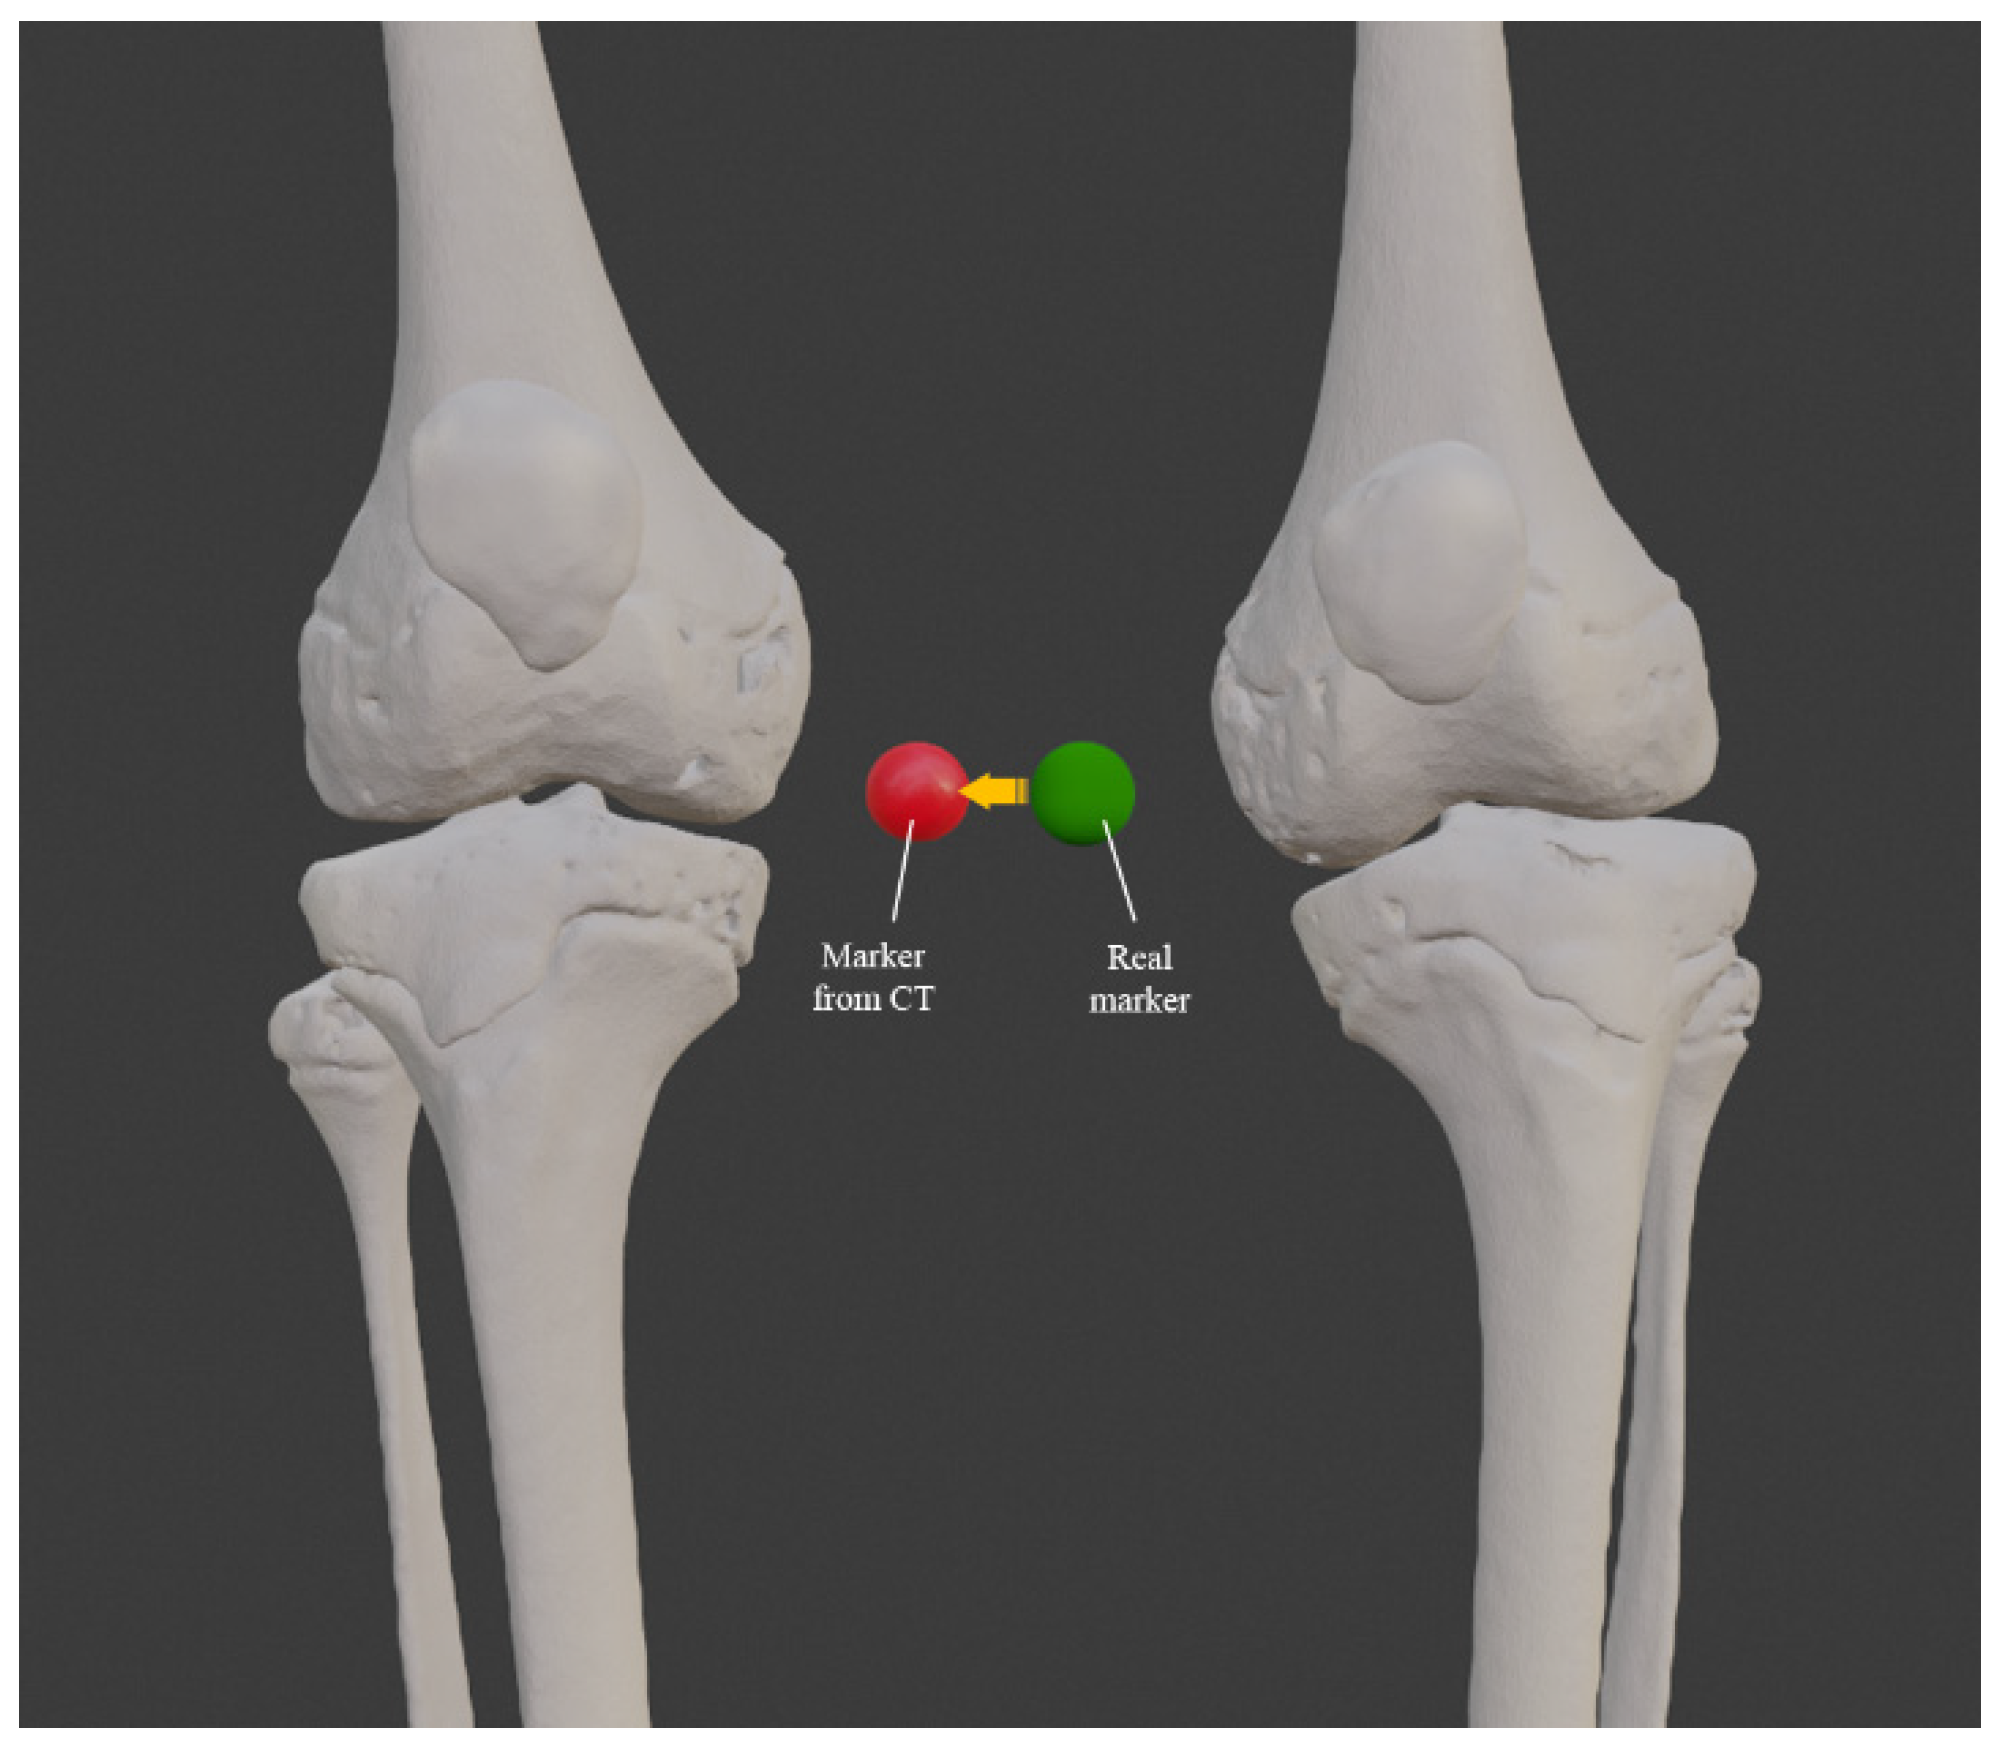

3.1. 3D Reconstruction of Patient-Specific CT Scan

3.3. Comparison between Standard and Custom Model